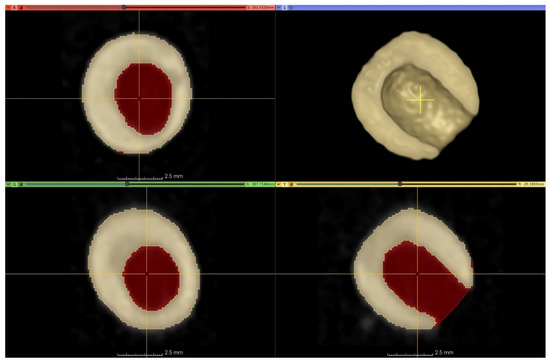

Computed tomography (CT) data collection was performed by Siemens Somatom Definition AS+ (Siemens, Erlangen, Germany) scanner using the settings as follows: tube voltage 100 kV, current 175 mAs, spiral data collection with pitch factor 0.7, collimation 128 × 0.6 mm. CT images were reconstructed of 40 “control” (C) and 40 “damaged” (D) peas arranged in a grid-like structure (8 rows, 5 columns) with 51 mm Field of View (voxel size of 0.996 × 0.996 × 0.1 mm).

The stored images in DICOM (Digital Imaging and Communications in Medicine) format were converted to NifTI (Neuroimaging Informatics Technology Initiative) format; then, every image processing step was performed in Python with open-source or custom-made software library and code. Otsu’s thresholding method was used in combination with morphological operators for producing initial binary masks (M1), which represents the actual state of the peas. Masks describing the approximated intact condition of the peas (M2) were created from M1 with additional “growing” morphological operators—thus, the voxels of M1 were a subset of M2’s voxels (Figure 5).

Figure 5.

Three-plane cross-sectional image and 3D-rendered representation of damaged peas by CT. The area of the lesion is marked in red in the cross-sectional images. The initial binary mask representing the actual volume of a pea (M1) marked with yellowish colour in the cross-sectional and the 3D-rendered image. The area of the lesion is marked with the reddish colour in the cross-sectional images. The mask approximating the intact condition of the peas (M2) is the union of the yellowish and the reddish areas on the cross-sectional images.